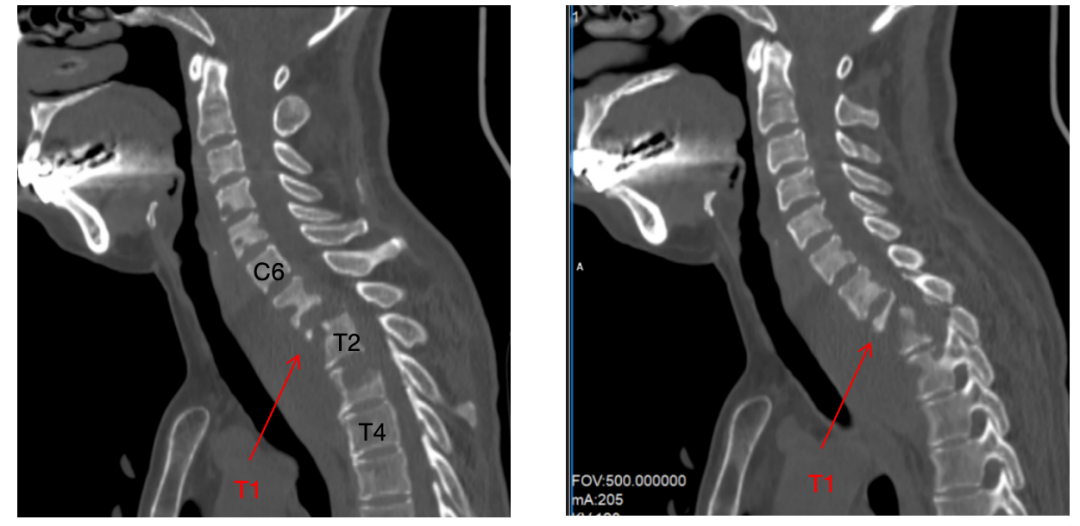

术后第一天,艾女士的双下肢活动能力便明显改善,颈部疼痛大幅缓解。在医护团队的精心照护下,通过高蛋白饮食调理、早期康复训练及精准用药,术后复查MRI显示脓肿基本清除(图4),患者双下肢肌力恢复4级。术后10天患者顺利出院。家属紧握医生的手感慨地说:“是你们的团队给了她重新站起来的机会!”

图4术后3月患者可在辅助下行走,未来康复的路还很漫长,衷心祝愿她能再一次用自己的脚步去丈量这个美丽的世界。